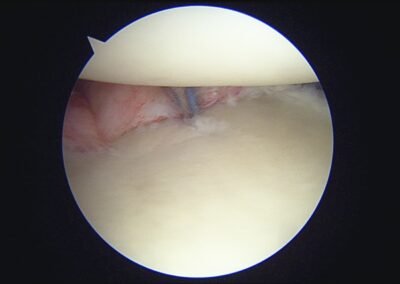

GalleryShoulder rotator cuff repair Meniscus root repair Meniscus repair Bankart repair for recurrent shoulder dislocation ACL reconstruction Machines Instruments